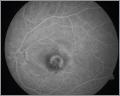

Photoaktivator (LASER) gegen feuchte Maculopathie |

Seit Zulassung der Behandlungsmethode PDT, (Photodynamische Therapie) im Jahr 2000, betreiben wir einen Photoaktivator zur Behandlung der feuchten Maculadegeneration und Verhinderung zentraler Erblindung mit dem Medikament Visudyne(Verteporphin) -->mehr

Hoffnung für Patienten mit der "feuchten Makuladegeneration" oder "pathologischer Myopie", die von zentraler Erblindung bedroht sind bringt die Photodynamische Therapie (PDT), ein Behandlungsverfahren, das seit etwa 20 Jahren in der Tumorbehandlung angewendet wird. Seit dem Jahr 2000 hat es in der Augenheilkunde ein neues Einsatzgebiet gefunden. In experimentellen Studien konnte zunächst gezeigt werden, daß durch die PDT auch isolierte krankhafte Gefäßneubildungen im Auge behandelbar sind. Dabei wird ein Medikament über das Gefäßsystem verabreicht, das sich in den neu gebildeten, veränderten Gefäßen, anreichert und nach Lichtbestrahlung seine besondere Wirkung entfaltet. Mit einem spezifisch auf den Farbstoff abgestimmten Laserlicht niedriger Intensität wird eine umschriebene, gewollte gewebsschädigende Reaktion ausgelöst, die zu einem Untergang proliferierender (wuchernder) Zellen führt. So ist es möglich, unter die Netzhaut gewachsene Gefäße zu verschließen, Flüssigkeitsansammlungen auszutrocknen und noch intakte Sinneszellen der Netzhaut zu erhalten oder sogar zu regenerieren. Behandlungsprinzip: Das Prinzip der Behandlung ist mit einem " 2 Komponentenkleber " vergleichbar. Keine der Komponenten wirkt allein- aber zusammengemixt sind sie hochpotent! Zum "Abdichten" der defekten Gefässe im Auge wird der Wirkstoff Verteporphin (Visudyne) mit einer Dosierpumpe über 10 Minuten in die Blutbahn gebracht. Der für dieses neue Therapieverfahren benutzte Farbstoff Verteporfin ist seit dem 16. Dezember 1999 in der Schweiz und seit dem 27. Juli 2000 in Deutschland zugelassen. Nach einer Verteilungszeit von 5 Minuten im Körper hat es sich in den Netzhautgefässen ausreichend angereichert. Jetzt genügt eine Aktivierung oder "Belichtung" mit einem unsichtbaren Laser (Photoaktivator) für 83 Sekunden unter mikroskopischer Kontrolle um die Abdichtung der undichten Blutgefässe zu erreichen.